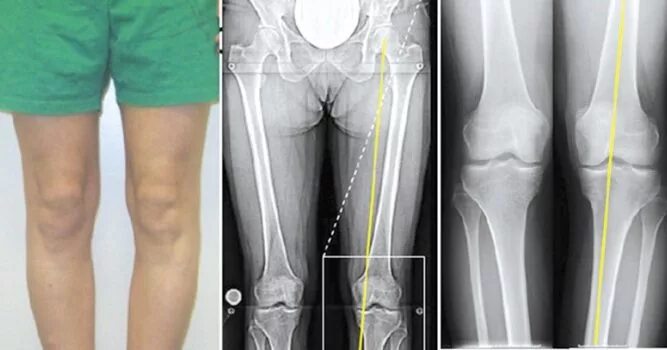

Гонартроз коленного сустава 3 степени как лечить